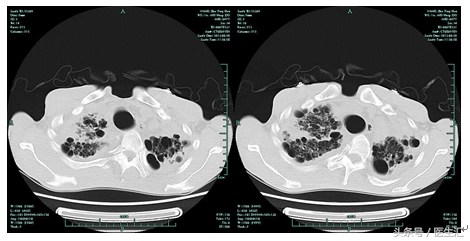

06-20肺CT平扫:

两肺间质性改变,肺气肿,两肺多发肺大泡。两肺上叶慢性感染机化。较2月12日CT大致相仿。